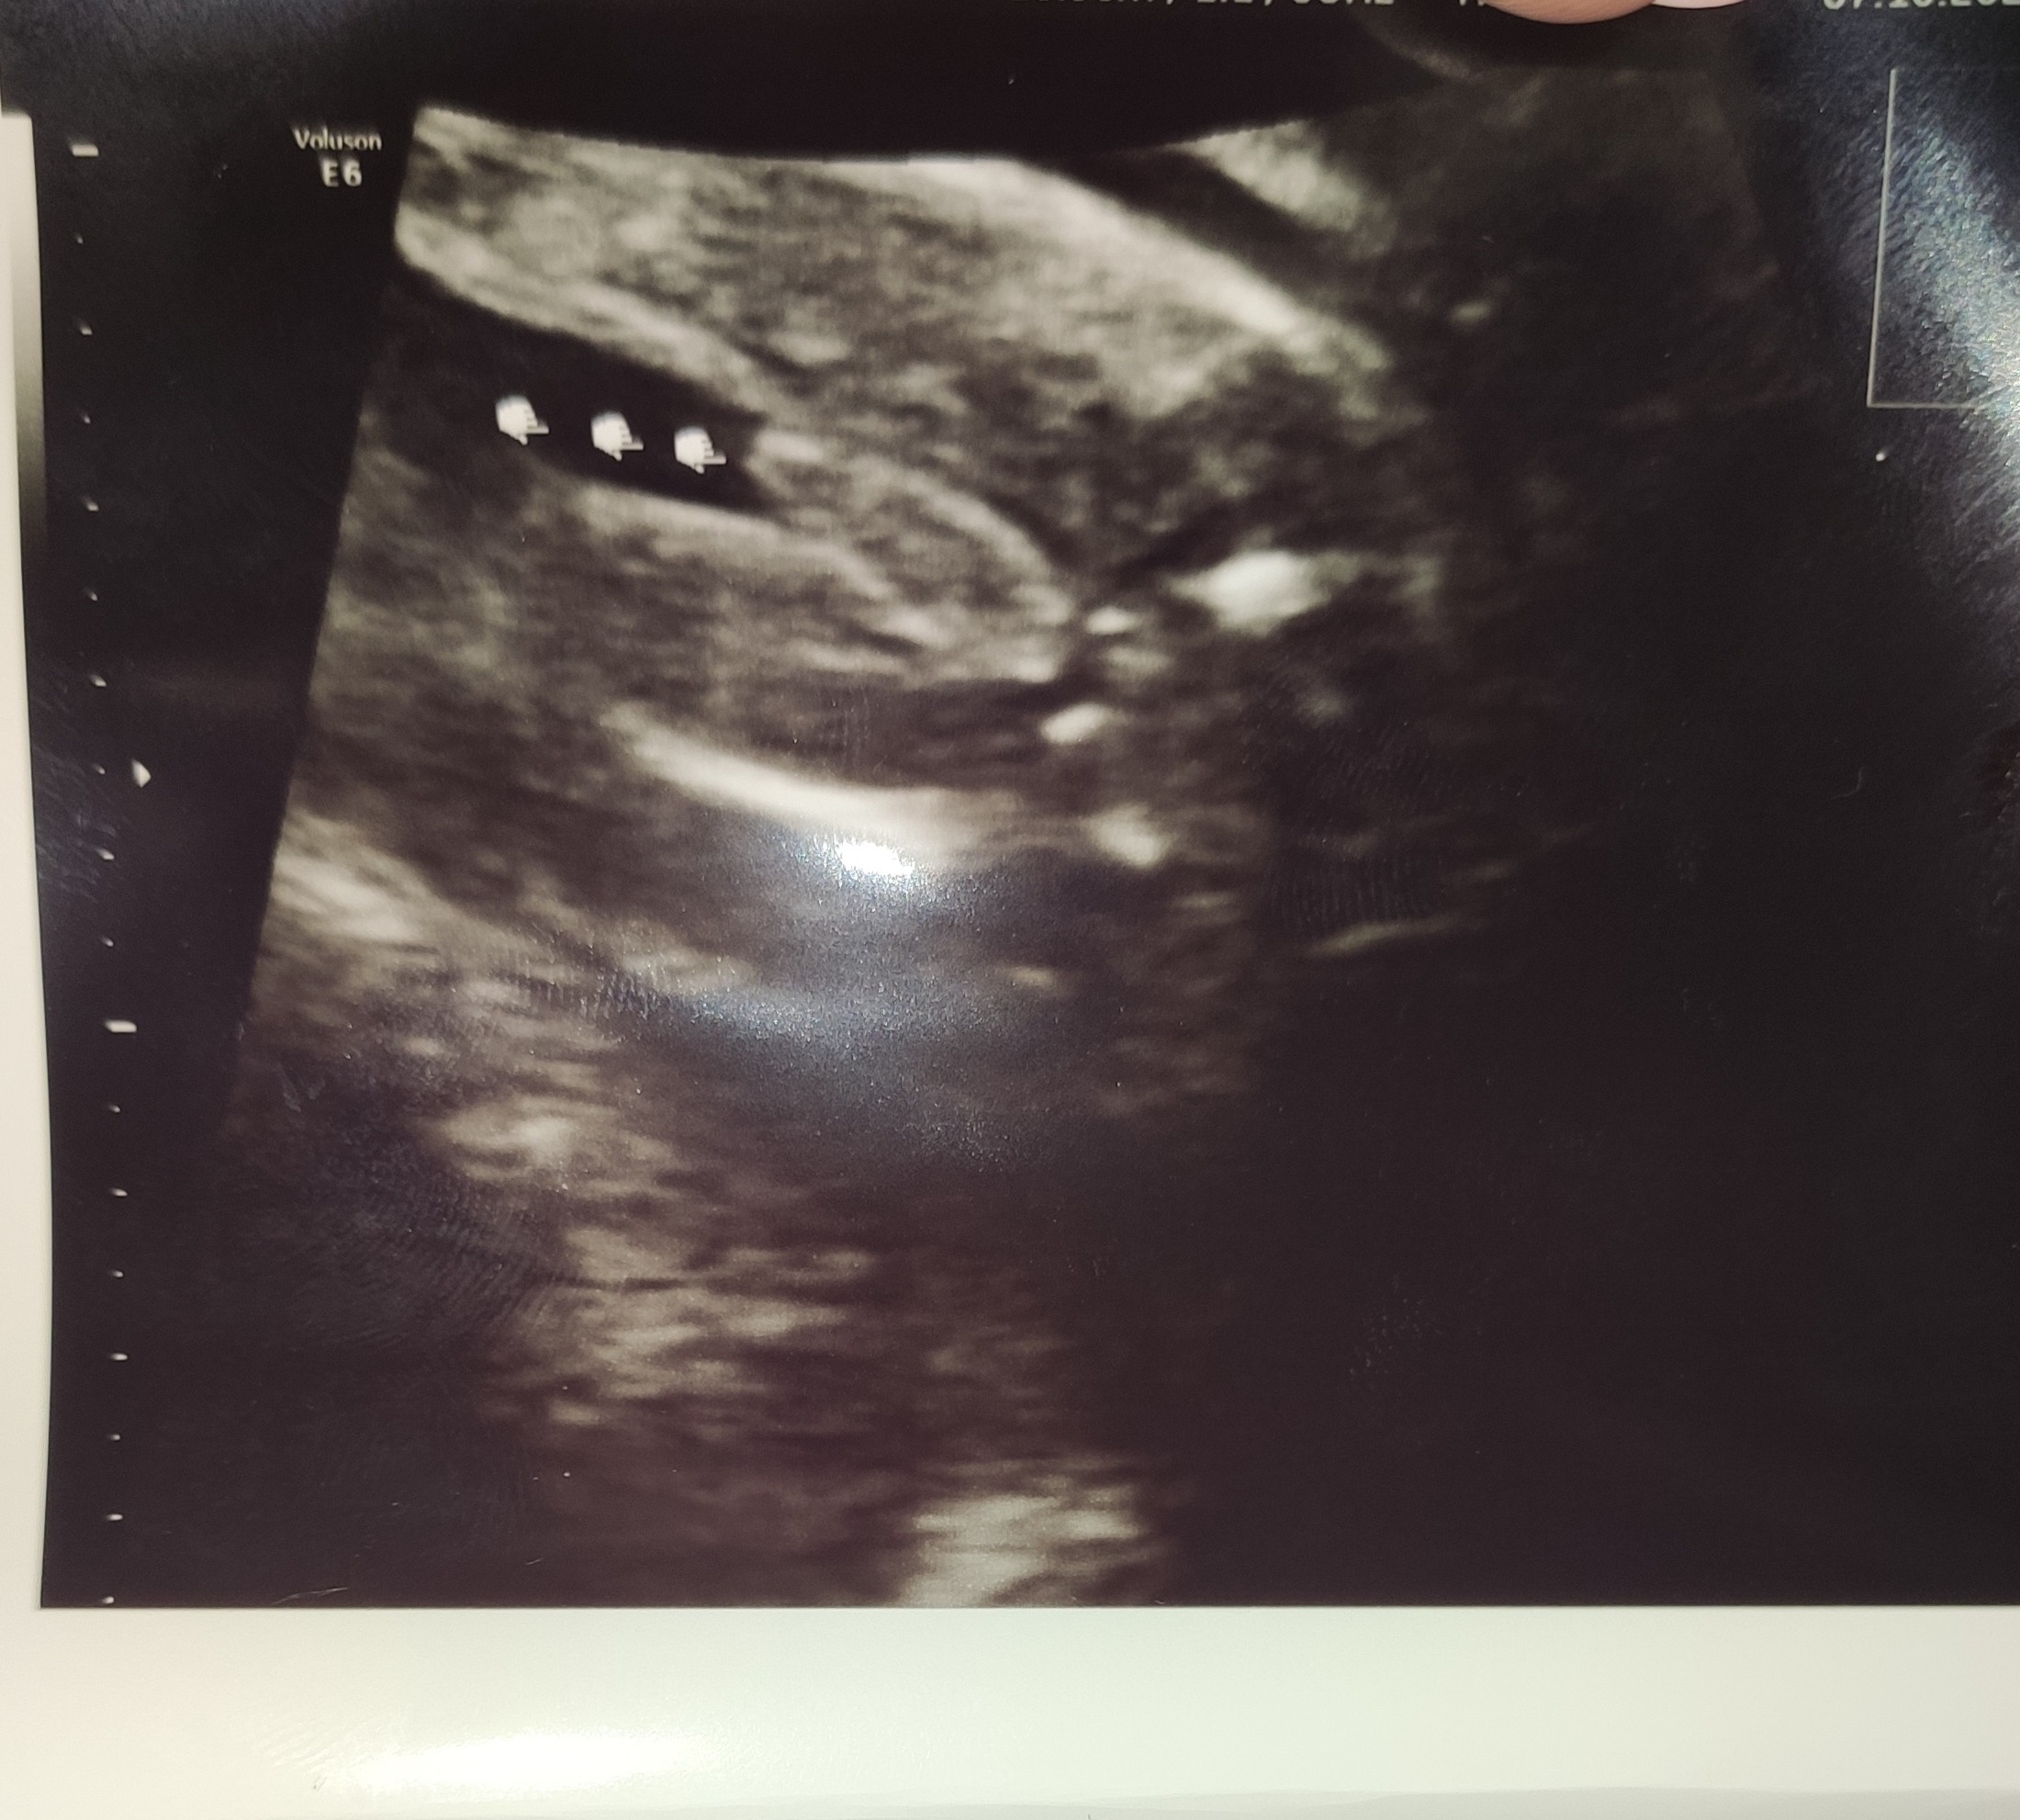

Cześć. Bardzo proszę Was o opinię. Jestem w 22 tygodniu ciąży. Mój ginekolog uważa, że będzie dziewczynka, natomiast na wczorajszych prenatalnych dowiedziałam się, że chyba będzie chłopak. Jednak ani jeden, ani drugi lekarz nie jest pewny na 100%. Jak myślicie? Chłopak czy dziewczynka?